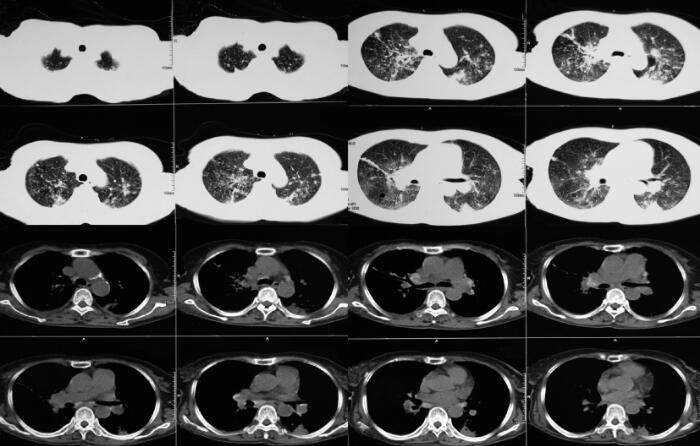

胸部CT:双肺多发斑片、结节影,以双肺上叶及下叶背段为主,多考虑肺结核;纵隔及肺门多发淋巴结肿大,部分钙化;左侧胸腔积液,双侧胸膜增厚(图1)。

图1 胸部CT

双肺多发斑片及结节影、纵隔及肺门淋巴结肿大,部分钙化